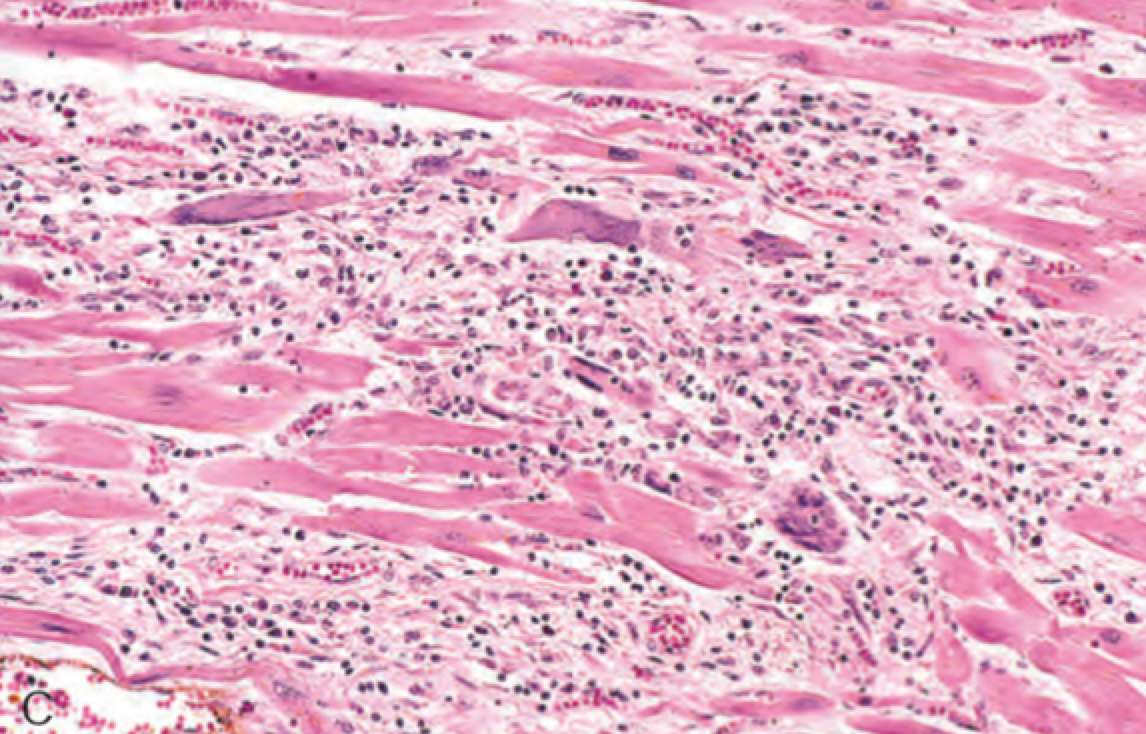

Межуточный миокардит: гистологические исследования

Раздел: Идеи и советы